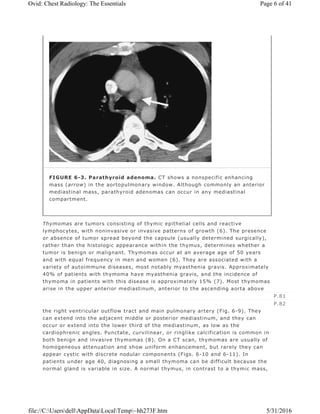

FIGURE 6-3. Parathyroid adenoma. CT shows a nonspecific enhancing

mass (arrow) in the aortopulmonary window. Although commonly an anterior

mediastinal mass, parathyroid adenomas can occur in any mediastinal

compartment.